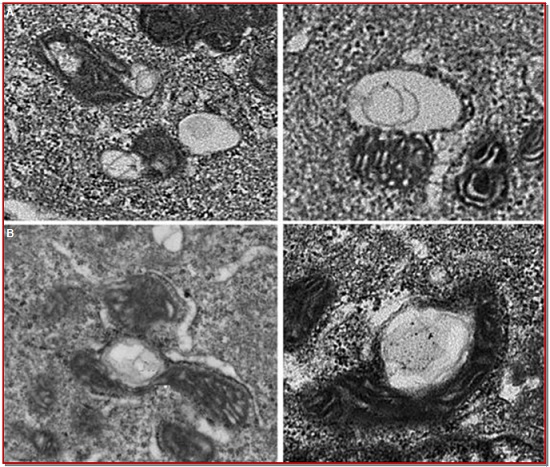

The study demonstrates the effect of vernolepin on proliferation and apoptosis in ovarian cancer cell lines. The inhibition of cell growth was significant at 30 ?M concentration after 48 hours in both OVCAR-3 and SK-OV3 cell lines. Phase-contrast microscopic examination revealed a decrease in number of vernolepin-treated cells. A number of membranous structures and vacuoles were visible in the cytoplasm after 24 hours. After 48 hours chromatin condensation and nuclear fragmentation indicating typical apoptotic changes were observed. Vernolepin treatment lead to 83.6% cell viability compared to control. However the cell viability was increased to 93.7% on after starvation followed by vernolepin treatment. On the other hand, 3-MA in combination with vernolepin decreased cell viability to 54.5%. Annexin V-FITC/PI staining and FACS demonstrated that in OVCAR-3 and SK-OV3 cells treatment with vernolepin (30 µ?) for 48 hours caused apoptosis in 34.2% and 28.5% cells respectively. Thus, vernolepin-treatment in ovarian carcinoma cells leads to autophagy before the onset of apoptosis and protects cancer cells.